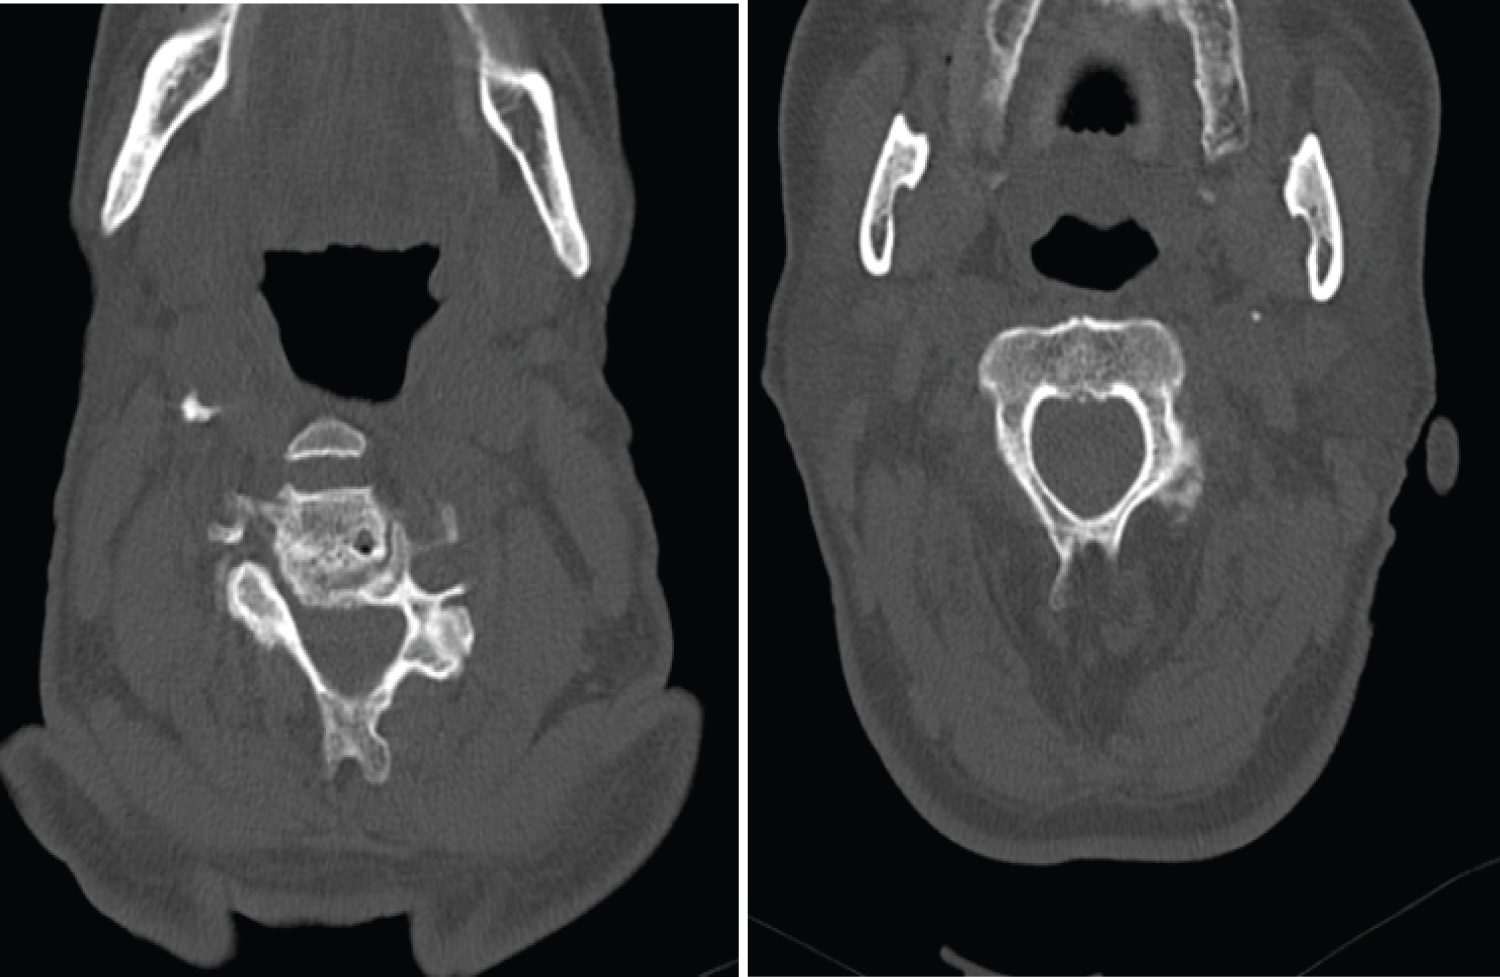

Magnetic Resonance Imaging (MRI) of the cervical spine showed stenosis with cord compression from C3 to C7 levels (Figure 1). Sagittal computed tomography image of the cervical spine showing ossified yellow ligament from c4 to c7 (Figure 2 and Figure 3).

Figure 2: Axial computed tomography image showing thickened nodular ossified yellow ligament.

Figure 3: Sagittal computed tomography image of the cervical spine showing an ossified yellow ligament.